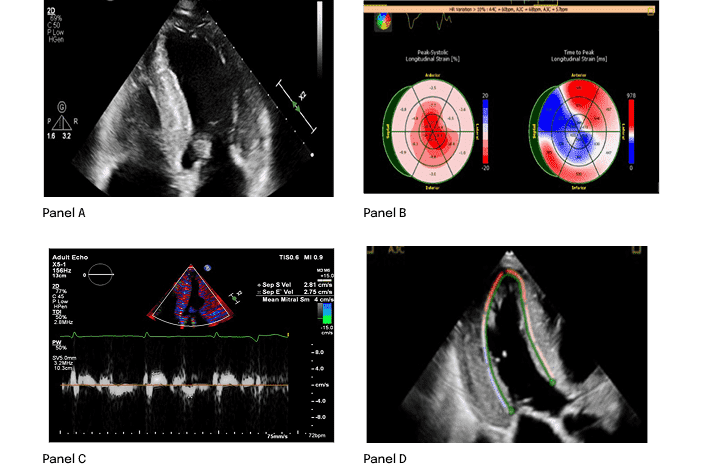

ECHO4

- Hypertrophic phenotype with infiltrative features

- Restrictive LV filling with RV wall thickening

- Low septal and lateral e′

- Reduction in global longitudinal strain